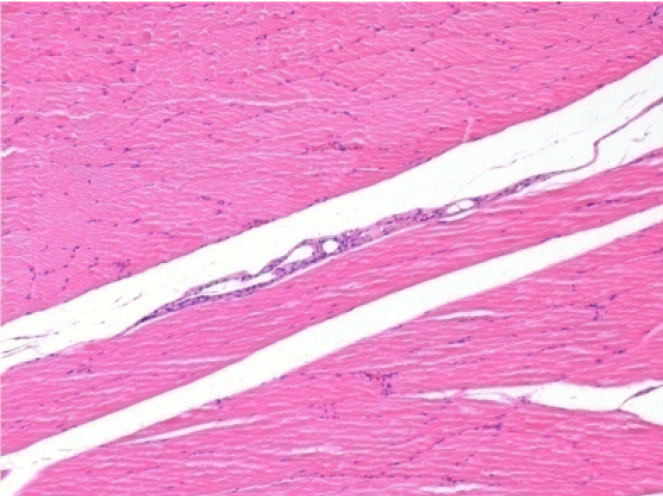

Sağ pretibial kasta 0,1 ml Endopeel Enjeksiyonundan 3 ay sonra (D90).

09

Endopeel, yaklaşık olarak 1 aylık bir periyotta seçici bir geri dönüşümlü miyofibroliz ve inflamatuar reaksiyonu indükler.

Kas değişiklikleri neredeyse tam olarak geri döndürülebilir